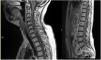

Los ganglioglioma son tumores bien diferenciados, de crecimiento lento, compuestos por una mezcla de células ganglionares maduras y gliales. La mayoría son de gradoI de la OMS. Aparecen predominantemente en niños y adultos jóvenes. La mayoría se localizan a nivel del lóbulo temporal, y la sintomatología más frecuente son las crisis epilépticas de difícil control farmacológico. En general tienen buen pronóstico tras la resección quirúrgica. La variante anaplásica, considerada gradoIII de la OMS, presenta mayor agresividad clínica y radiológica. La diseminación leptomeníngea es excepcional en estos tipos de tumores, pero cuando es diagnosticada presenta un curso rápidamente progresivo y fatal para el paciente.

Gangliogliomas are well-differentiated, slow-growing tumors. The majority are gradeI of WHO. It appears predominantly in children and young adults. Most are located at the temporal lobe, and as symptomatology more frequent epileptic seizures of difficult pharmacological control. In general, they have a good prognosis after surgical resection. The anaplasic variant, considered to be gradeIII of the WHO, presents greater clinical and radiological aggressiveness. Leptomeningeal dissemination is exceptional in these types of tumors, but when diagnosed it presents a rapidly progressive and fatal course for the patient.